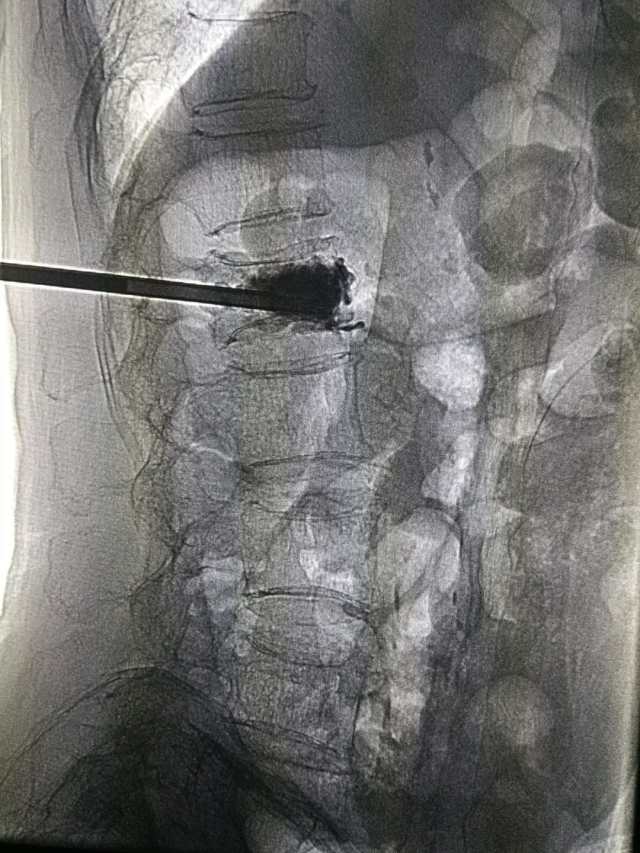

老人前几日突然感到腰部疼痛,起立及翻身活动时加重,平躺休息时疼痛才稍稍减轻,在家吃了几天药,但不见什么效果,而且疼痛逐渐加重,在市三院经过腰椎核磁扫描后,显示为「腰 1 椎体压缩骨折」,结合老人的身体状况,医生推测很可能因为骨质疏松引起了骨折。

经过患者家属同意后,脊柱外科为其实施了「经皮椎体后凸成形术」,术后患者恢复良好。